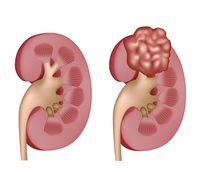

سرطان الكلى

مقالة مفصلة: سرطان الكلى

| سرطان الكلى | ||

| معدل الانتشار | 208.500 عالمياً [14] | |

| معدل البقاء 5 سنوات | 73% (الولايات المتحدة) [10] | |

| حالات الوفاة | 13.570 (عالمياً، 2013) [15] | |

| عوامل الخطورة | خطر الإصابة عند الذكور ضعف ما عند النساء، وعند المدخنين ضعف ما عند غيرهم. يزداد خطر الإصابة ببعض أنواع المرض بسبب زيادة الوزن. معدلات الإصابة بسرطان الكلى أكبر عند العاملين بالأسبست والعاملين في أفران فحم الكوك. | |

| العلامات المنذرة | وجود دم في البول، ورم (كتلة) في منطقة الكلية، وَجَع كليل dull ache أو ألم pain في الجانب أو الظهر، أحيانا علامات أخرى مثل ارتفاع ضغط الدم أو شذوذ في عدد خلايا الدم الحمراء. | |

| الكشف والتشخيص | صور شعاعية للكلى، شاملة الحَقْن بالصبغة dyes؛ التصوير الطبقي التفرسي المحوسب (CT scans)؛ التصوير التفرسي بالرنين المغنطيسي (MRI scans)؛ تصوير الشرايين الشعاعي؛ الفحوص بالأمواج فوق الصوتية، وقد يُحتاج إلى الخزعة لتأكيد التشخيص.

| |

| العلاج | تتم بإزالة كامل الكلية المصابة أو جزء منها، وتكون عادة مع الغدة الكظرية المجاورة. ويمكن استخدام المعالجتين الشعاعية والانصمامية embolization ـ وهي إجراءٌ لسد الأوعية الدموية ـ للتخفيف من شدة الأعراض. تمّت الموافقة على استعمال الإنترليوكين وهو مادة لها دور في الجهاز المناعي، ولكنها تؤدي إلى تأثيرات جانبية سُمية خطيرة.

| ملاحظات | شهدت أمريكا الشمالية أعلى معدلات انشار سرطان الكلى، في حين كانت المعدلاات في آسيا وأفريقيا هي الأصغر.[16] | |